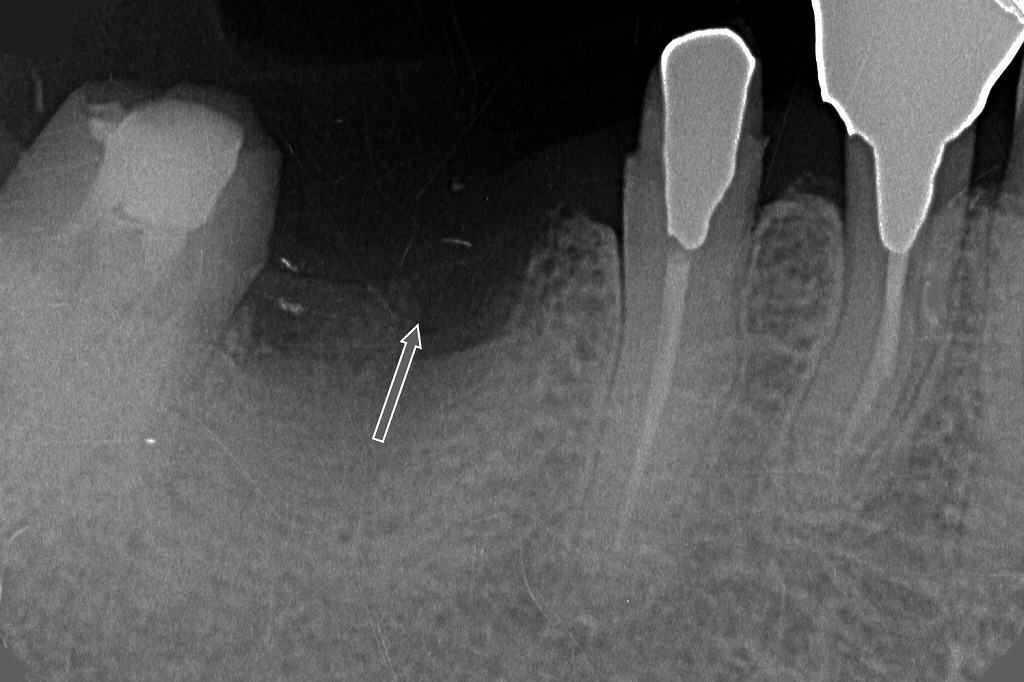

⑤下顎6番抜歯後の抜歯窩を示すX線所見

画像中央の矢印で示された部位には、下顎6番(第一大臼歯)を抜歯した後の抜歯窩(ソケット)が認められます。

抜歯窩(ソケット)の特徴

矢印の領域は、周囲骨よりも**透過性が高く(黒く)**写っており、

これは抜歯直後〜初期治癒過程に特有のX線像です。

抜歯後しばらくは、

- 血餅(血の塊)

- 線維性組織

- 新生骨がまだ未成熟

であるため、骨がまだ十分に白く写りません。

隣在歯の状態

抜歯した6番の**近心側(5番)と遠心側(7番)**は正常に残存しています。

歯根膜腔の幅や歯槽骨に異常な透過像はなく、6番以外に周囲病変はみられません。

抜歯理由との整合性

この症例の流れは、

- 根分割

- 遠心根の破折

- 支台喪失

- → 抜歯

という経過です。

画像は、破折により保存不可能と判断された6番を抜歯した直後の明瞭な所見です。

今後の補綴方針

抜歯後は、

- 7番・5番を支台としたブリッジ

- インプラント治療

- 部分義歯

などが選択肢になります。

抜歯窩の治癒が進むにつれて、数ヶ月かけて徐々に白く(骨で)満たされていきます。